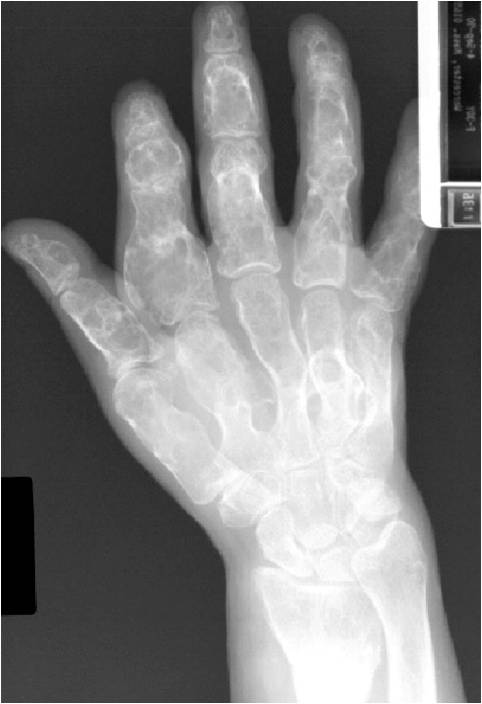

- 50% involve hands and feet (mostly phalanges)

- Cortex may be scalloped and thinned in the phalanges

Geographic lesion, Stippled calcifications in lesion, Phalanx is expanded, Significant endosteal scalloping, No cortical destruction, No soft tissue extension, Cortex Scalloped and Expanded